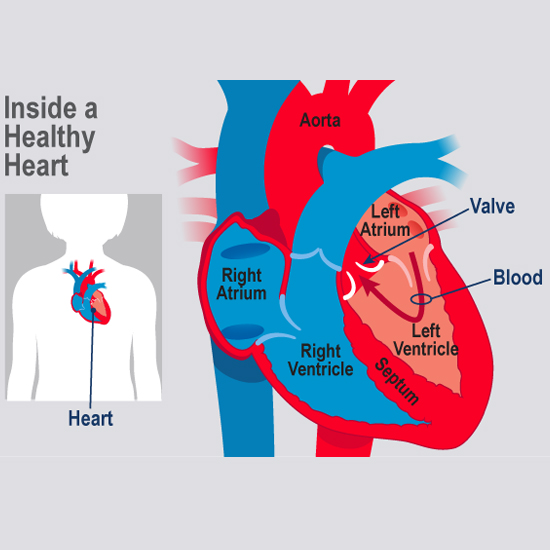

Balloon Mitral Valvotomy (BWM) used to increase the opening of narrowed (stenotic) valve.

Treatment Of Atrial Septal Defect(ASD) which is a congenital heart defect in which blood flows

Treatment Of Ventricular Septal Defect (VSD) which is a defect in the ventricular septum,